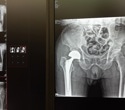

open-heart surgeryImage Credit: MAD.vertise/Shutterstock.com